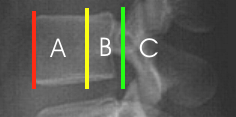

- 3) Beurteilung des Alignments:

- vorderer Wirbelkörperlinie

- hintere Wirbelkörperlinie

- Spinolaminäre Linie

- 4) Physiologische Weichteilbreite

- Höhe A: max. 7 mm

- Höhe B: max. 22 mm

- 5) Physiologische Abstände zwischen Atlasbogen und Dens (C)

- bei Erwachsenen: 2,5 - 3mm (CAVE: Kann bei rheumatoider Arthritis vergrößert sein)

- bei Kindern 3 - 4mm